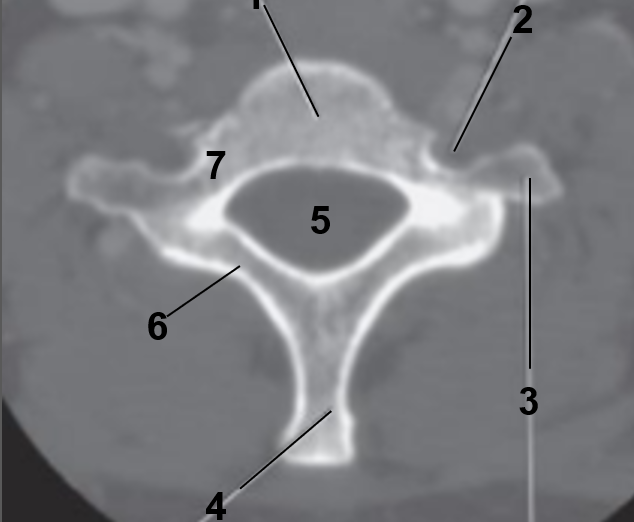

1

Transverse foramen

2

Anterior arch

3

Transverse Process

4

Posterior arch

5

Superior articular facet

6

Dens

7

Vertebral Foramen